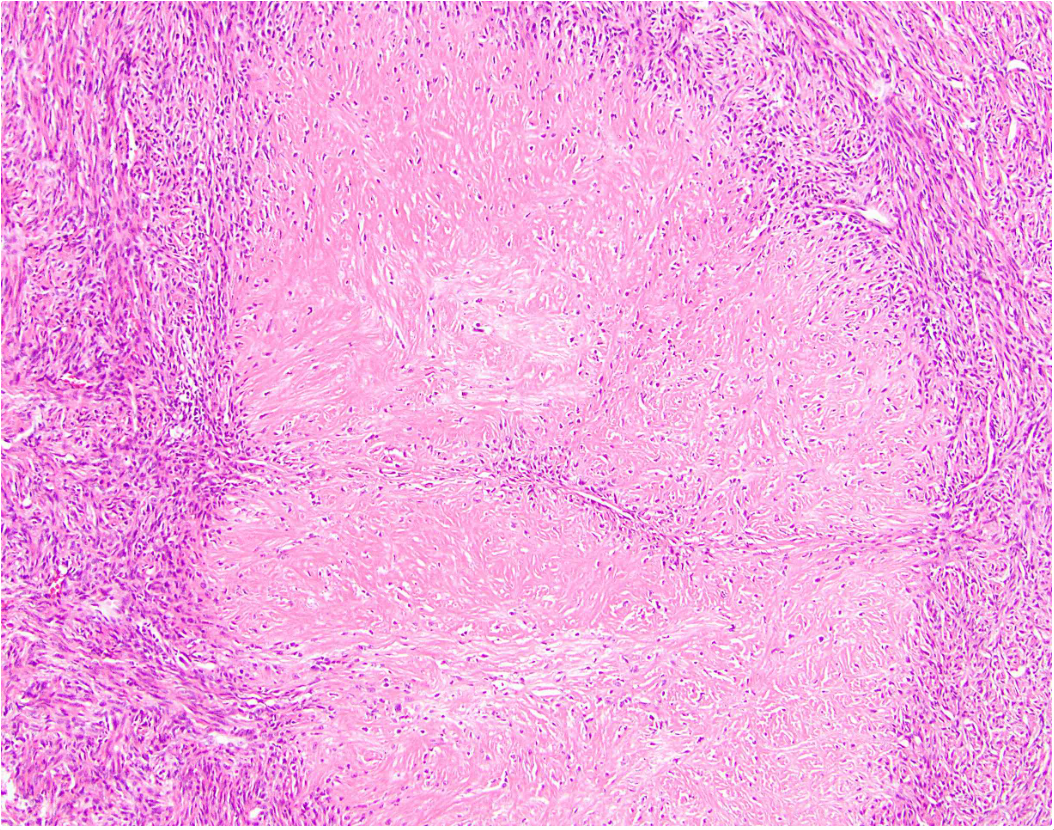

37F thigh lesion

Desmoid fibromatosis

Essential: long, sweeping fascicles of bland fibroblasts and myofibroblasts without substantial cytological atypia; infiltrative growth.

Desirable: nuclear β-catenin expression; characteristic CTNNB1 mutation (in challenging cases or small biopsies).